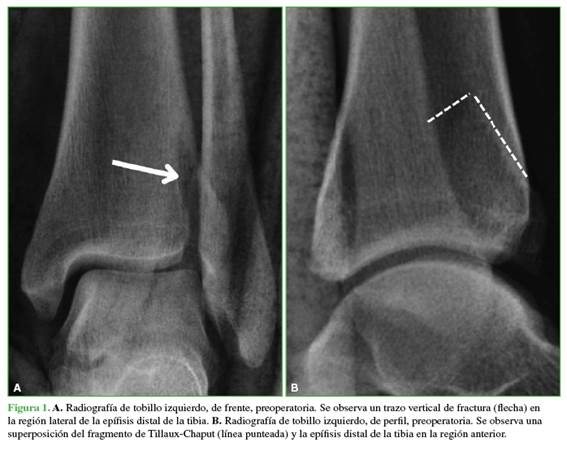

Mujer de 45 años, sin antecedentes médicos de relevancia, que sufrió un traumatismo de tobillo izquierdo con un mecanismo rotatorio. Fue atendida inicialmente en el Servicio de Urgencias. En el examen físico, se observó la imposibilidad para cargar sobre ese miembro, impotencia funcional en el tobillo, y leve edema y dolor localizados en la región anterolateral. El examen neurovascular fue normal. Se solicitaron radiografías de tobillo, de frente y de perfil que mostraron un trazo de fractura en la región anterolateral distal de la tibia (Figura 1). Para confirmar la fractura, se solicitó una tomografía computarizada que reveló una fractura aislada en la región anterolateral de la tibia, correspondiente al tubérculo de Tillaux-Chaput (Figura 2).